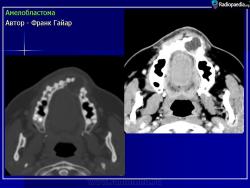

Амелобластома

ID: 9430 Ameloblastoma Dr Frank Gaillard - 16 Apr 2010 Ameloblastoma resected en-blocAuthor: Berto1286Original files:http:...

КТ сканирование шеи